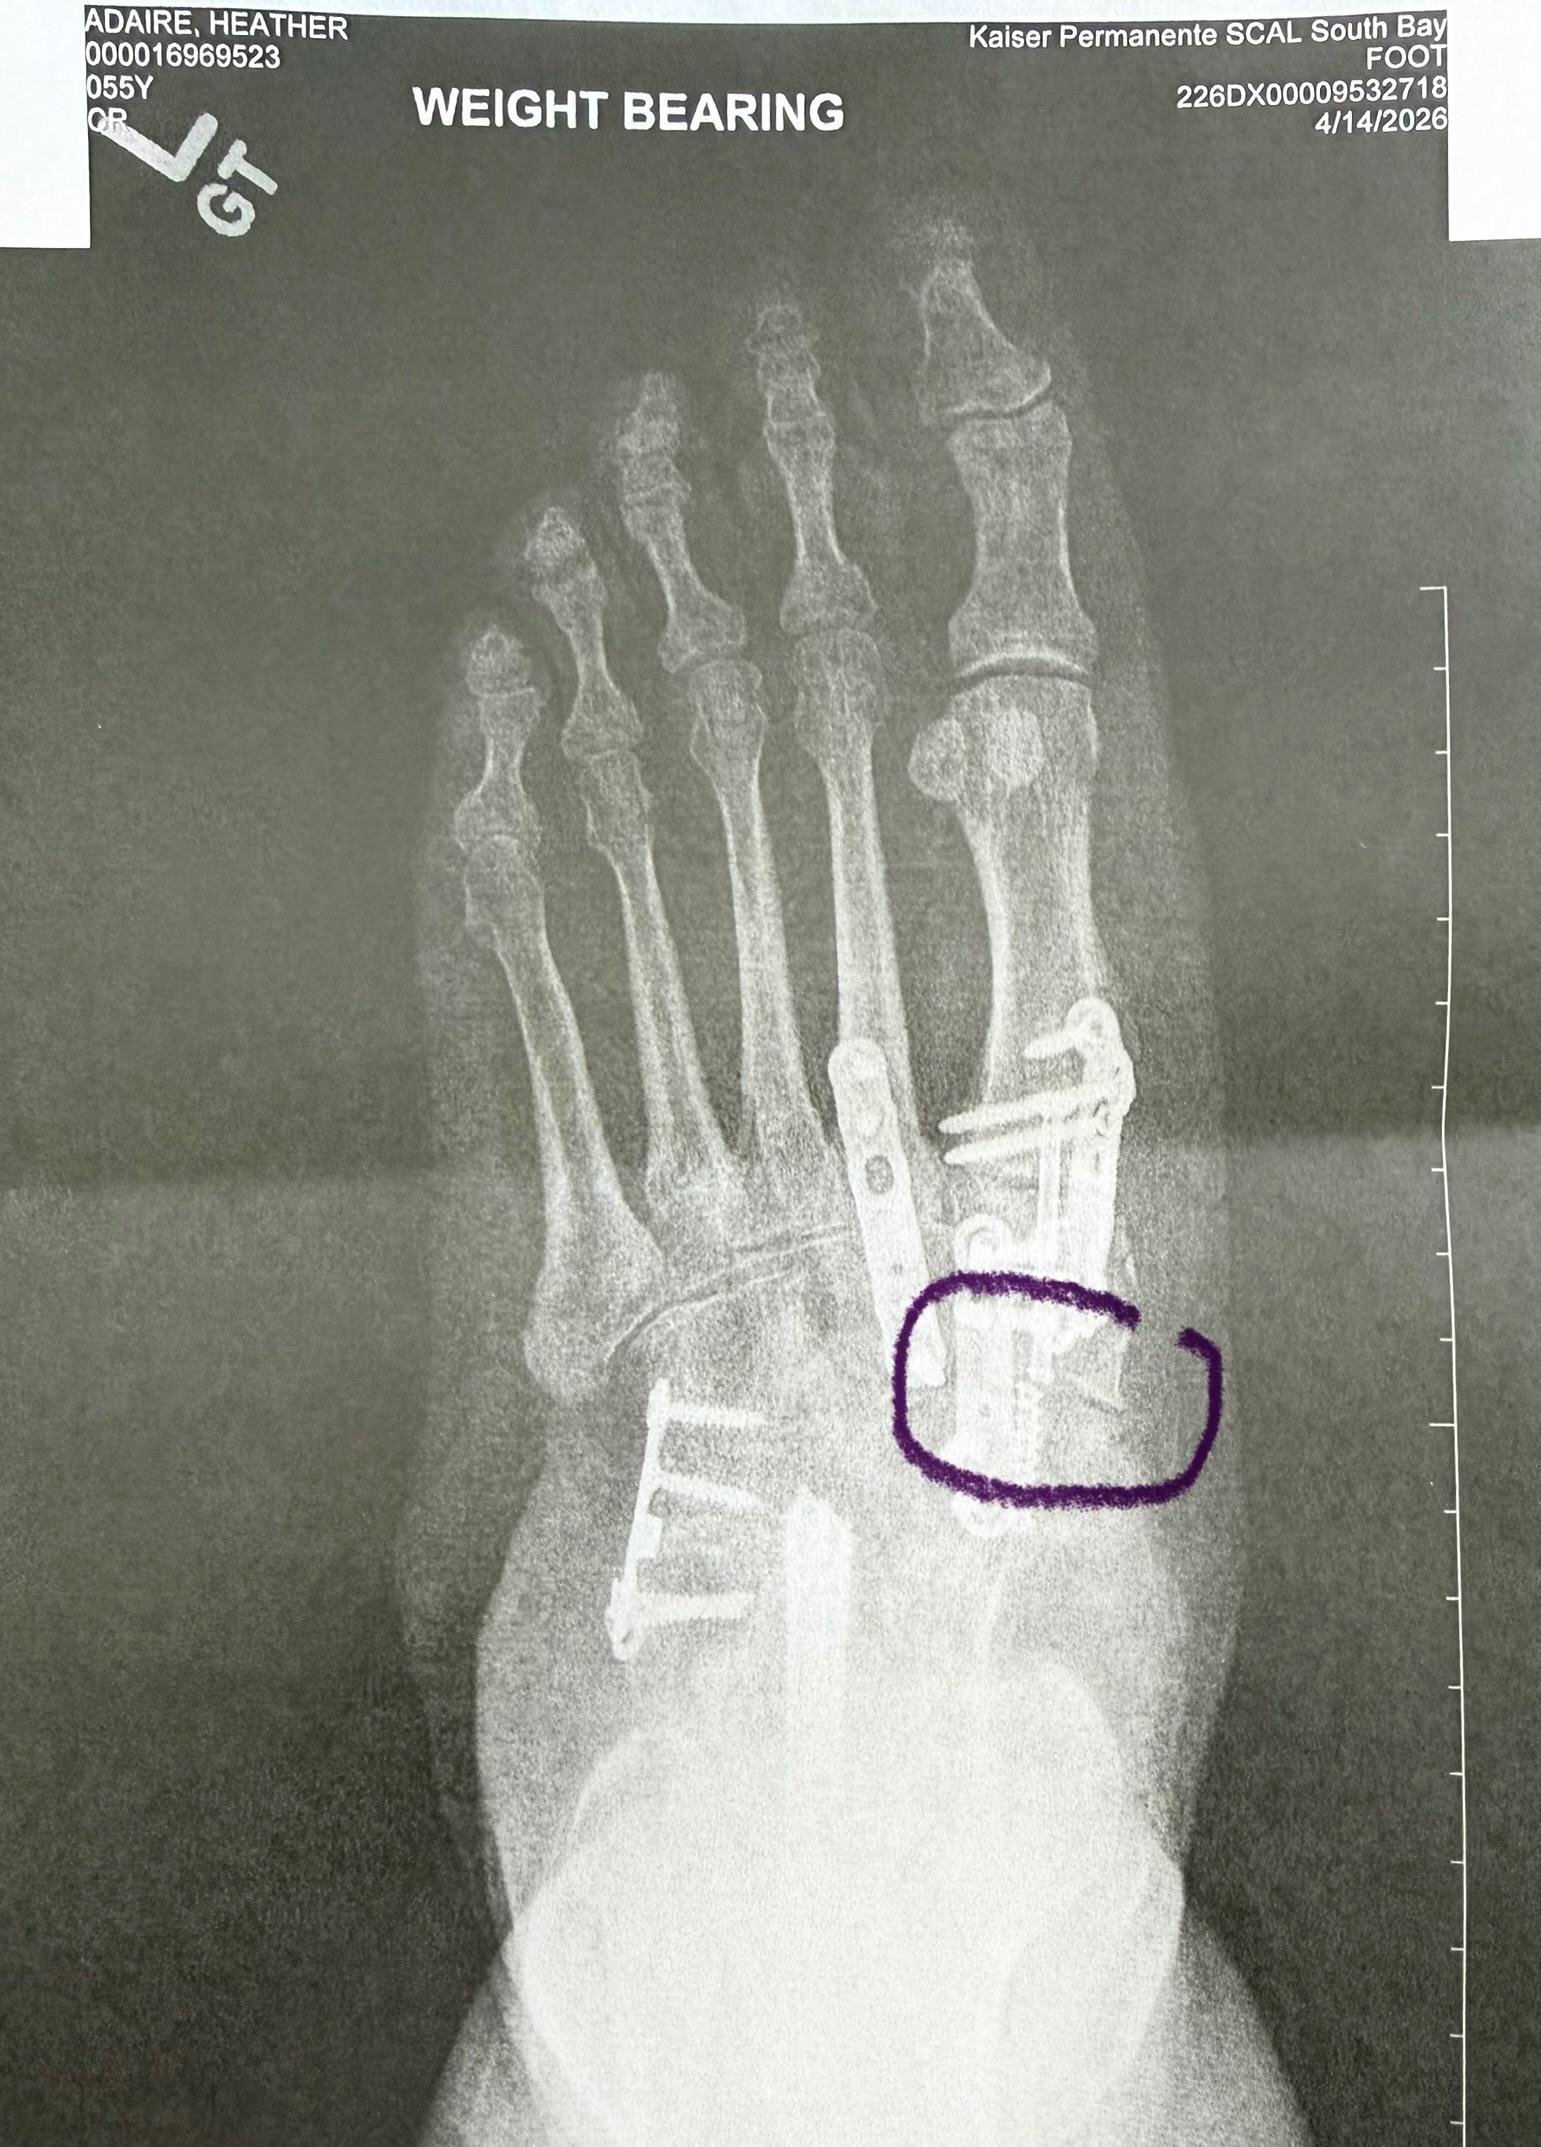

Over the past several months, I have faced a series of unexpected medical challenges. After undergoing surgery, I experienced complications that led to multiple trips to the emergency room. Just as I was hoping to recover, I learned that I need another surgery to repair broken hardware in my foot, which will take place on June 3rd. This news has been overwhelming, especially since it means I will be unable to work for at least six months while I heal.